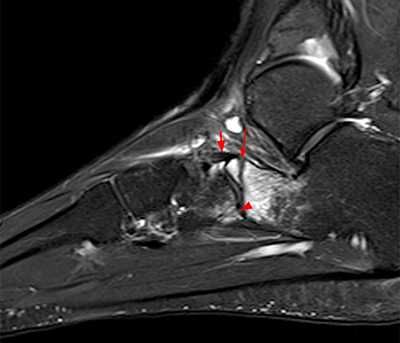

Пациент М. 1980 г.р., травму получил при падении на стопы с высоты 1,5 метра. Лечился по месту жительства (в травмпункте районной больницы) консервативно в гипсовой повязке в течение 14 дней. Консультирован в травматологическом отделении ФГБУ «УНИИТО им. В.Д. Чаклина» Минздрава РФ, предложено оперативное лечение. При поступлении кожные покровы стопы чистые, без признаков воспаления и сдавления тканей. Стопа отечна, уплощена. На рис. 1 представлены рентгенограммы пациента. Прооперирован через 2 недели после травмы. Операция состоит из двух этапов. Первый этап заключается в наложении дистракционного аппарата. Проводятся две спицы 1,8 мм во фронтальной плоскости: первая через нижнюю треть диафиза большеберцовой кости, вторая через бугор пяточной кости (рис. 2). Спицы фиксируются в дистракционном аппарате, выполненном из двух полуколец, соединенных между собой двумя телескопическими тягами. Особое расположение полуколец, фиксация спиц на концах полуколец, крепление кронштейнов для телескопических тяг обеспечивает тракцию пяточной кости в необходимом направлении с использованием минимального количества спиц и внешних опор при сохранении необходимого поля обзора для проведения рентгенологического и визуального контроля репозиции и фиксации. Второй этап - закрытая элевация импрессированной суставной поверхности и окончательная репозиция пяточной кости. Через разрез длиной до 1 см по латеральному краю ахиллова сухожилия (рис. 3) в месте его прикрепления к пяточной кости под соответствующий фрагмент подводится элеватор (рис. 4), манипуляцией которым устраняется смещение и выполняется провизорная фиксация спицами 1,5 мм (рис. 5). При сагиттальном раскалывании суставной фасетки целесообразно проведение одного-двух винтов субхондрально (рис. 6). Стержень вводится с дорзальной поверхности пяточной кости по ее оси через разрез до 2 см по предварительно сформированному остеотомом каналу (рис. 7, 8). Далее через проколы кожи с помощью кондуктора (рис. 9) выполняется запирание винтами с латеральной поверхности, внешнее устройство демонтируется. Достигнуто удовлетворительное стояние отломков (рис. 10).

Рис. 1. На рентгенограмме левой стопы в прямой и боковой проекциях определяется оскольчатый внутрисуставной перелом левой пяточной кости

Рис. 3. Под контролем ЭОП из разреза длиной до 1 см латеральнее места прикрепления ахиллова сухожилия выполняется элевация суставной поверхности пяточной кости

Рис. 4. Устранение смещения отломка

Рис. 5. Провизорная фиксация репонированной суставной поверхности спицами

Рис. 6. Окончательная фиксация компрессирующим винтом, введенным субхондрально